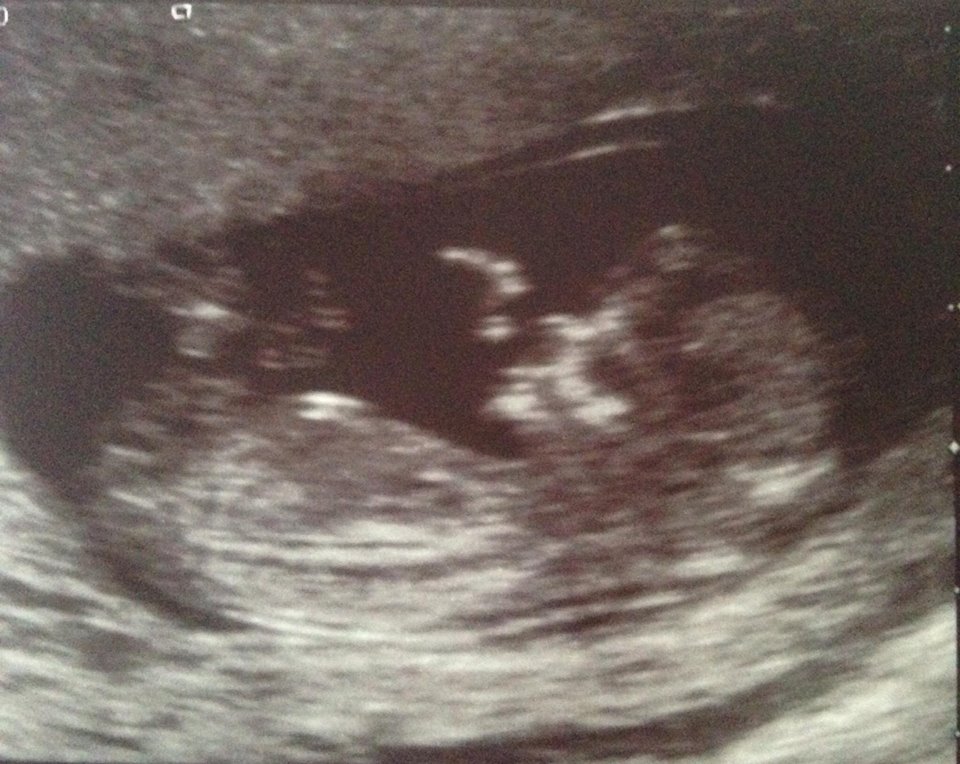

Hope this works...would love any guesses on gender.

I can't make out anything clear down there but cute baby!

Not sure I see anything but nothing sticking up either so I'll guess girl